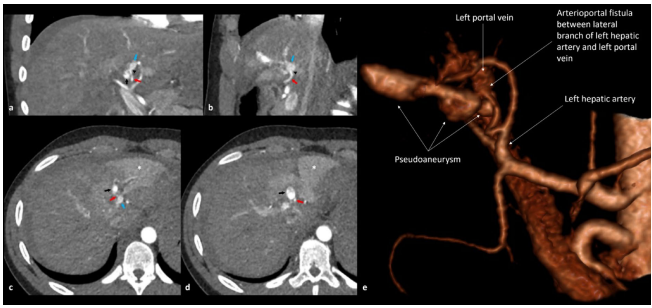

高处坠落(28.6%)和机动车事故(MVA)(30.6%)是导致肝脾联合损伤的主要原因。图3展示的案例中,180km/h车速导致的碰撞不仅造成脾脏活动性出血,还引发了肝右动脉分支的假性动脉瘤。